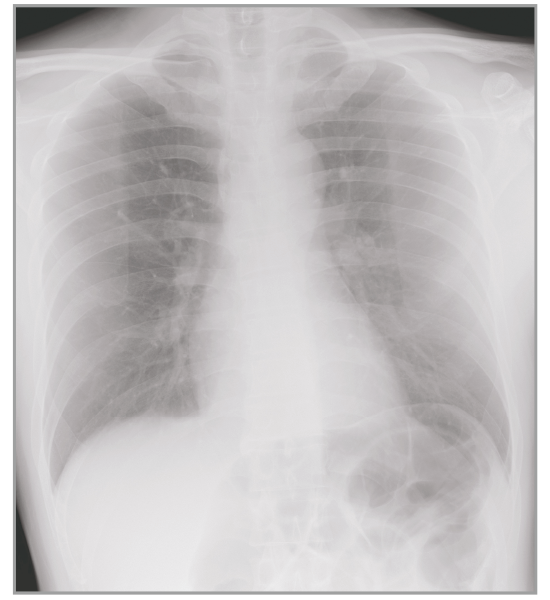

Multiple body parts supported

Abdomen

Cervical Spine

Thoracic Spine

Lumber Spine